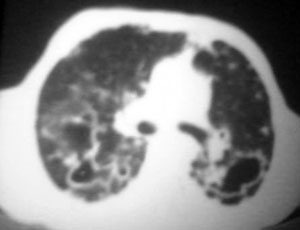

以下是引用逸风在2006-9-12 14:57:00的发言:[br]ct显示双肺上叶点片状及纤维索条状密度不均影,肺野外带近胸膜可见大小不等的含气空腔,壁略厚,境界清晰,未见液平面,中下肺野散在小片状及点状高密度影;纵隔内显示点状钙化,未见明显淋巴结肿大,构成胸廓诸骨未见明显异常.[br]诊断意见:1.双肺结核合并支气管播散;2.双肺上肺大泡.